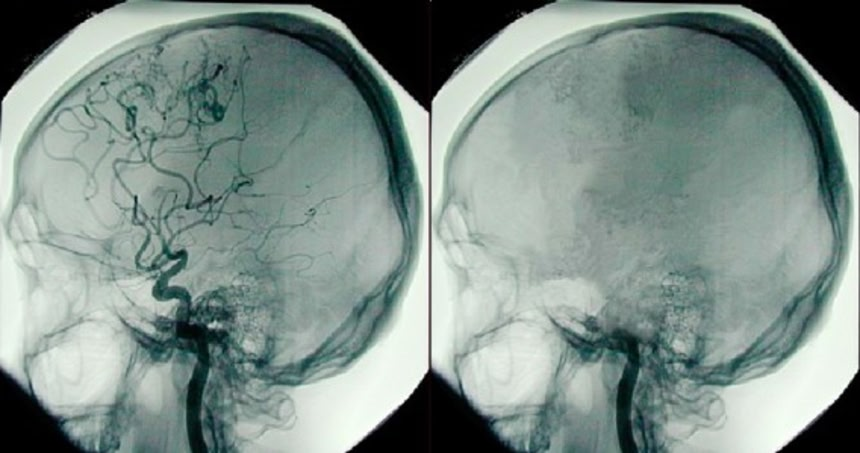

この画像を大きなサイズで見るこれまで、超常現象に分類されることも多かった「臨死体験」だが、その謎にまた一歩近づいたようである。心臓麻痺を起こし死の淵に立った人が時に経験する、まぶしい光などの鮮明な「臨死体験」は、科学的に説明できるかもしれないとする研究論文が12日、米科学アカデミー紀要(PNAS)に掲載された。脳は血流が停止した後も30秒程度、活動を続けることが分かったという。

研究を行った米ミシガン大学の科学者らは、実験用ラット9匹に麻酔薬を投与して心停止を誘発させ、脳電図を記録した。その結果、心臓が停止してから30秒間にわたり脳の活動が急増し、精神状態が非常に高揚していることが分かった。

「臨死状態では、意識がある状態を示す電気信号の多くが覚醒状態のレベルを上回っていたことが分かった。これは、臨床死の初期段階において、脳が系統立った電気活動を行うことが可能であることを示唆している」。同様の結果は、窒息状態のラットの脳活動にもみられたという。

この画像を大きなサイズで見る論文の主著者、ジモ・ボルジギン氏は、「心停止中の酸素の減少、または酸素とブドウ糖の減少によって、意識的過程の特徴である脳活動が刺激される可能性が、この研究で示された。また、心停止を経験した多くの患者が語る臨死体験を説明するための、初めての科学的枠組みが提供できた」と話す。

これまで、心停止から蘇生した患者の約20%が、医師らが「臨床死」と呼ぶ段階でなんらかの視覚的な経験をしたと報告している。